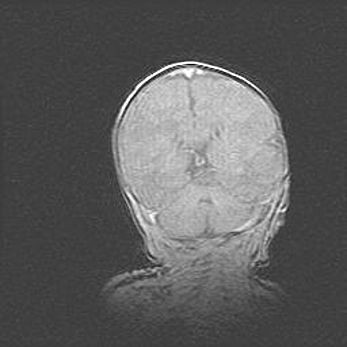

Аномалия Денди-Уокера. Признаки гипоплазии мозолистого тела.

Возраст: 5 месяцев 3 дня

Вес: 5550 г

Пол: мужской

Окружность головы: 39 см

Срок гестации: 40 недель

Аномалия Денди-Уокера – это порок развития головного мозга, для которого характерна триада симптомов: гипотрофия или аплазия червя мозжечка и/или полушарий мозжечка, расширение четвёртого желудочка с формированием ликворной кисты задней черепной ямки, гипертензионная гидроцефалия различной степени.

Гипоплазия мозолистого тела относится к дефектам внутриутробного этапа развития мозговой ткани, возникающим в процессе закладки структур головного мозга, что происходит на начальных этапах развития эмбриона.